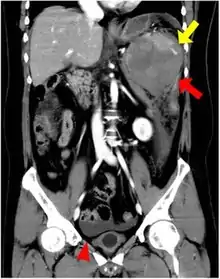

If splenectomy is performed for conditions in which blood cells are sequestered in the spleen, failure to remove accessory spleens may result in the failure of the condition to resolve.[1] During medical imaging, accessory spleens may be confused for enlarged lymph nodes or neoplastic growth in the tail of the pancreas,[5] gastrointestinal tract, adrenal glands or gonads.[2]